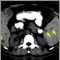

Lymph node metastases, CT scan